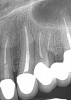

(17.) Case 3 initial radiograph of bridge on Nos. 6 through 9 and crown on No. 10.

Figure 17

(18.) Case 3 initial radiograph of bridge on Nos. 6 through 9 and crown on No. 10.

Figure 18

A 42-year-old man presented with a very loose bridge on Nos. 6 through 9 with periodontally compromised retainers on Nos. 6 and 9 (Figure 17 through Figure 19), and endodontically involved No. 10 with a calcified canal. Teeth Nos. 6, 9, and 10 were extracted, the sockets fully debrided, and pontic soft tissue on Nos. 7 and 8 sculpted to be symmetrical in soft tissue contour with the contralateral lateral incisor and central incisor locations. Implants were secured in position Nos. 6 through 10 (Figure 20) in excess of 45 Ncm, the bone was milled to provide unimpeded seating of temporary abutments, and temporary crowns were fabricated chairside and adjusted to be out of occlusion in centric relation and all excursions. The temporary crowns were cemented after extrusion of excess cement extraorally and the patient was prescribed antibiotics, analgesics, and instructed in postoperative care particular to immediately provisionally restored implants. At 6 months, integration was confirmed (Figure 20 through Figure 23) and after placement of scanning abutments, the implants and soft tissues were scanned. Final crowns were fabricated from the scanned images and were cemented after extrusion of excess cement extraorally (Figure 24 through Figure 26), and oral hygiene procedures were reviewed.